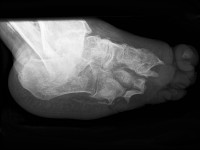

![Neuropathische voet bij lepra (click on photo to enlarge) [source: www.huidziekten.nl] Neuropathische voet bij lepra](../../../images/neuropathische-voet-lepra-1z.jpg) |

![Neuropathische voet bij lepra (click on photo to enlarge) [source: www.huidziekten.nl] Neuropathische voet bij lepra](../../../images/neuropathische-voet-lepra-2z.jpg) |

![Neuropathische voet bij lepra (click on photo to enlarge) [source: www.huidziekten.nl] Neuropathische voet bij lepra](../../../images/neuropathische-voet-lepra-3z.jpg) |

| neuropathische

voet |

neuropathische

Behandeling van de neuropathische voetDe patiënten

worden meestal begeleid door de revalidatie arts, die ook de

neuropathische voet bij diabetes

behandelt. De patiënten moeten goed geïnstrueerd worden hoe schade door heet

water en door druk en andere trauma te voorkomen. Er moeten zachte ruime gymschoenen

met dikke zolen worden gedragen of speciale orthopedische schoenen worden aangemeten

die ruimte geven aan de tenen, en met een inlay zool die kan worden aangepast

aan drukpunten. Bij een acuut drukulcus kan eventueel een loopgips (total contact

cast) worden aangebracht voor enkele weken, om de druk te verdelen over de hele

voetzool. Er kunnen tijdelijke Pullman sloffen met aangepaste zolen worden verstrekt.

Callus rond en op drukulcera moet regelmatig worden verwijderd. Dit kan een

ervaren doktersassistente of verpleegkundige doen, of de podotherapeut. Ondermijnde

wondranden bij ulcera moeten worden weggesneden (dit kan zonder verdoving).

Ulcera worden in zijn algemeenheid behandeld door het wegnemen van de druk in

combinatie met normale wondverzorging. Plantaire ulcera kunnen worden getransplanteerd

met punchgrafts maar als daarvoor punches van het bovenbeen worden gebruikt

dan blijft die huid kwetsbaar omdat deze huid genetisch anders is dan de dikke

verhoornende huid van de voetzool. Punches uit de voetrand of uit de ingroeiende

epitheelrand van het ulcus differentiëren wel tot stevige huid. Verder is het

belangrijk om alert te zijn op infectie en osteomyelitis. Ontsteking in botten

kan worden opgespoord door met de handrug te voelen naar warmte. Vaak zijn er

ook huidveranderingen zoals hyperpigmentatie, papillomatose, pseudo-epitheliomateuze

hyperplasie. Met een röntgenfoto en of MRI of botscan kan de infectie zichtbaar

worden gemaakt. Bij osteomyelitis is soms nog conservatieve behandeling met

antibiotica mogelijk. De duur van de behandeling is minimaal 6 weken. Mogelijke